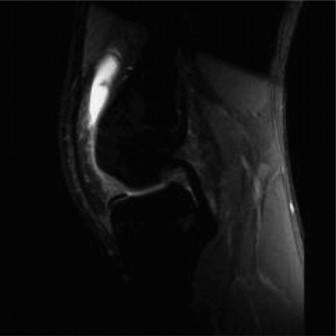

The MRI is obtained, and the patient returns with his parents to review the images (Figs. 10–27 and 10–28).

Figure 10–27

Figure 10–28 The diagnosis most consistent with the images shown in Figures 10–27 and 10–28 is:

The correct answer is (A). The patient has sustained an ACL tear. Once thought to be uncommon amongst pediatric populations, recent studies have shown these injuries are frequently encountered. A tibial eminence avulsion fracture is of concern in adolescent patients, though there is no evidence of injury at this location. The axial view of the patella shows no injury to the medial patellofemoral ligament or bone marrow edema at the patella or femoral trochlea which are signs of a possible patellar dislocation. The medial meniscus is intact.